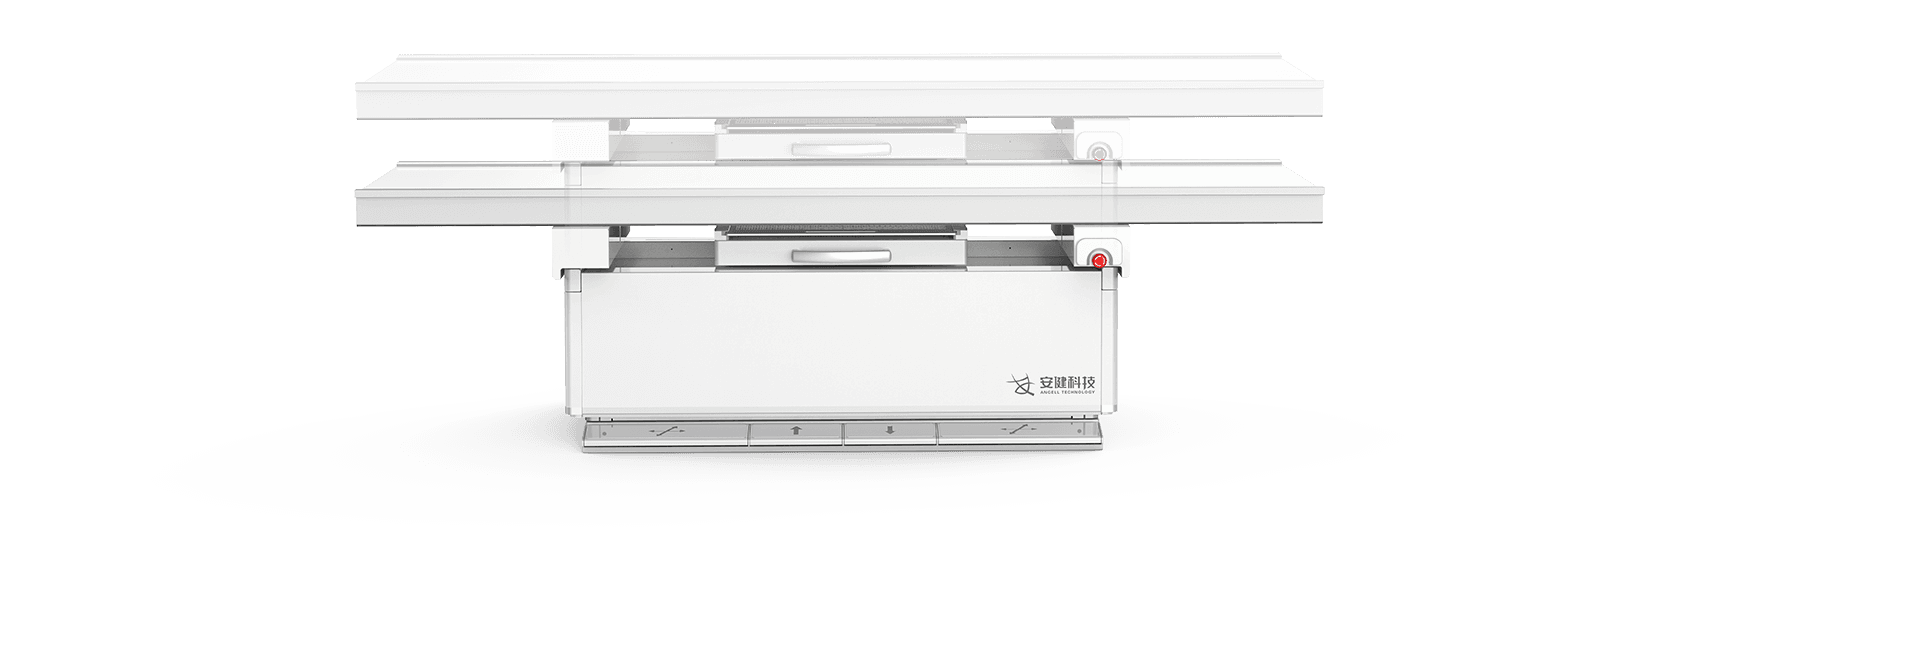

¶а№¦ДЬРьµхКЅ»ъРµФЛ¶ЇЈ¬И«ЖЅєвОИ¶ЁРФЙијЖЈ¬4DК®ЦбБЄ¶ЇјјКхЈ¬»ъјЬФЛ¶ЇЧФИзЖЅОИЈ¬

ЕдєПµз¶ЇЙэЅµґІј°¶а№¦ДЬБўКЅЙгУ°јЬЈ¬ЗбЛЙВъЧгБЩґІИ«МеО»ЙгУ°РиЗуЎЈ

µз¶ЇЙэЅµґІ

і¬ґуРРіМФЛ¶Ї·¶О§Ј¬Бй»оУ¦¶Ф¶щНЇЎўАПИЛЎўНвЙЛ»јХЯЙППВґІЎЈ

Ед±ёЗ¶ИлКЅёРУ¦ЅвЛшПµНіЈ¬ЗбЛЙµчЅЪґІёЯІўУРР§±ЬГв»јХЯО󴥡Ј

ЗбЛЙёЯР§ІЩЧчБч

¶а№¦ДЬРьµхКЅ»ъРµФЛ¶ЇЈ¬И«ЖЅєвОИ¶ЁРФЙијЖЈ¬4DК®ЦбБЄ¶ЇјјКхЈ¬»ъјЬФЛ¶ЇЧФИзЖЅОИЈ¬

ЕдєПµз¶ЇЙэЅµґІј°¶а№¦ДЬБўКЅЙгУ°јЬЈ¬ЗбЛЙВъЧгБЩґІИ«МеО»ЙгУ°РиЗуЎЈ